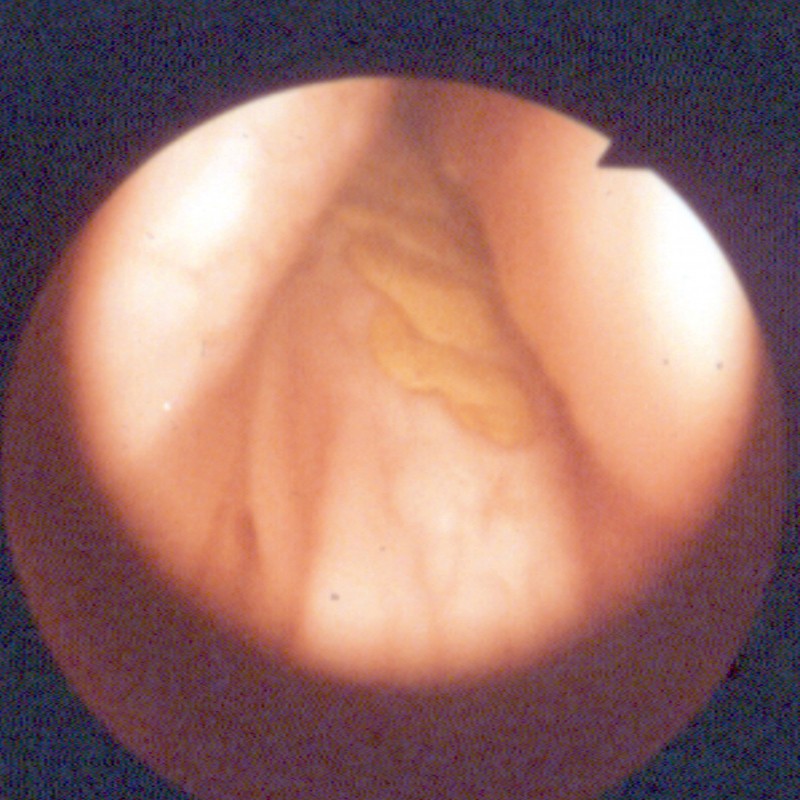

FM de 30 ans les 2ème et 3ème pm ont quitté l'arcade mandibulaire...